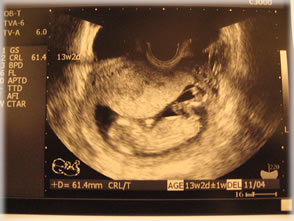

初公開ちびごろり。

baby.jpg

この日の1週間前の映像。

この日のはなんかぼやーっとしてたので・・・。

足が2本ちゃんとあるでしょ^^